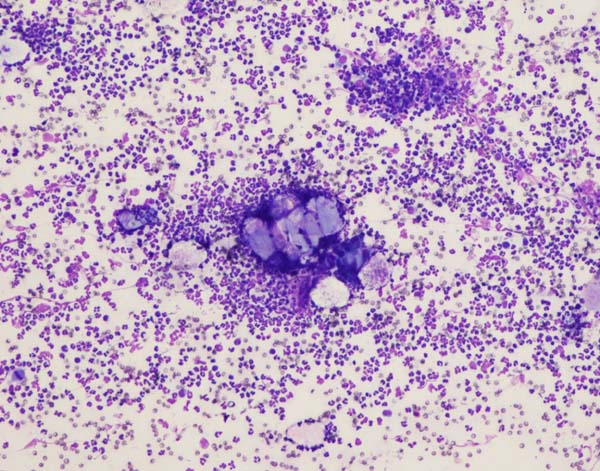

ワンちゃんが乳腺にできた複数のシコリを気にされて来院されました。bilateral mastectomyで対応しました。摘出後の病理組織検査の結果は、「R3-4間腫瘤:乳腺癌(複合型)」でそれ以外は「良性乳腺混合腫瘍」でした。無事元気に退院し、その後再発もなく経過は良好です。よかったね。